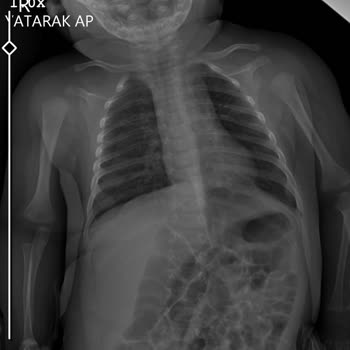

Saat 21.00 sularında çocuğum ateşlendi, ateşi 38,5 olunca önce duş aldırdım, sonra Calpol verdim ama ateşi düşmeyince en yakın hastaneye götürdüm. "Baz Ekol Sada Menemen" Hastanesi'nde nöbetçi çocuk doktoru olduğunu öğrenince doğrudan oraya gittim. Hastaneye girdiğimde saat 22.40'tı, özellikle kont...